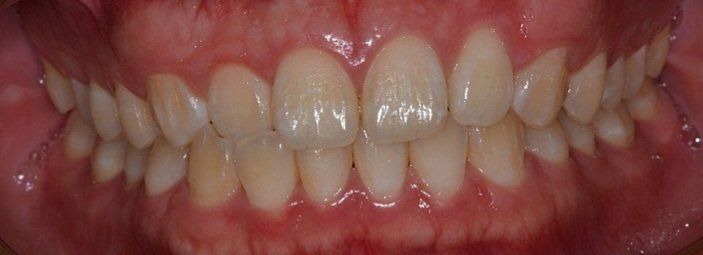

A치과) 상악에 비해 하악이 긴편이나 정상범위라고 볼수 있어 주걱턱은 아니라고 봅니다. 그래서 수술적 치료는 필요치 않아 보입니다. 치아상태는 전치부 총생 및 전방경사가 있고 상악 우측절치 반대교합이 있다 장기적으로는 좋지못하다. 앞니 부분교정 또는 인비절추천

대부분의 경미한 부정교합은 사람마다 있습니다. 치축 경사나 여러가지 상황을 보았을 때 정상범주이며 일부 양쪽 턱관절이 비대칭으로 발생한 턱관절 틀어짐으로 보여집니다. 이 역시 정상범주이며 예민하신 분이 아니라면 살아가는데 크게 불편감이 없어 보입니다. 인비절라인을 하더라도 크게 개선되지 않을 수 있어 보이며 신중하게 하셔야 할 것으로 보입니다.